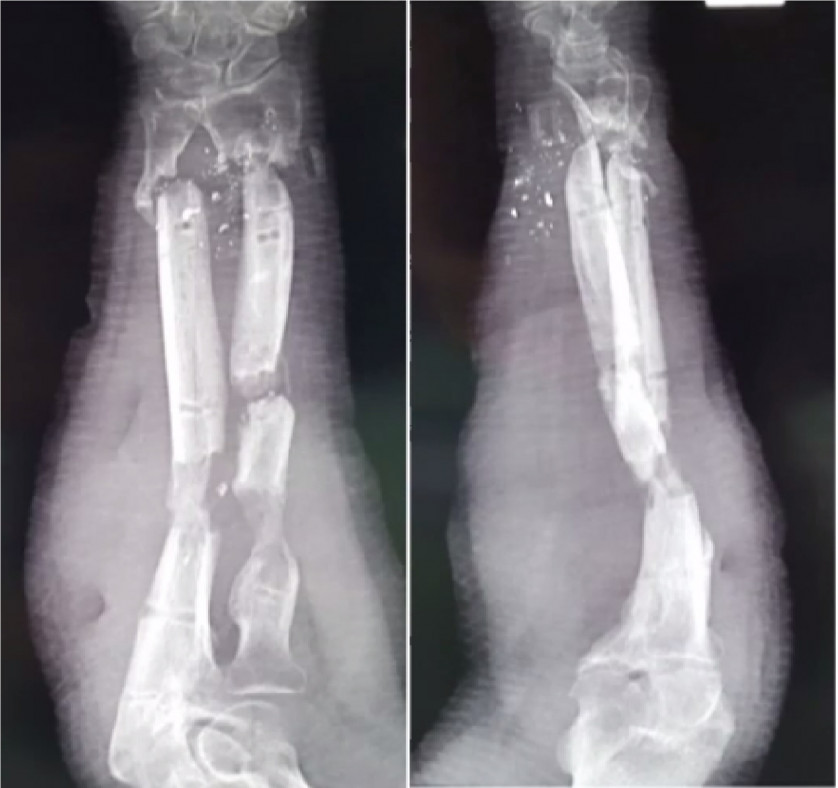

Что такое перелом лодыжки?

Лодыжкой называют дистальный отдел малоберцовой и большеберцовой кости (соответственно латеральная и медиальная лодыжка), который выполняет важнейшую функцию: стабилизирует голеностопный сустав.

Они образуют вилку голеностопа, которая удерживает и распределяет вес всего тела человека.

На переломы лодыжки приходится около 15% от всех случаев переломов костей. Они бывают одно-, двух- и трёхлодыжечными (в последнем случае наблюдается также перелом заднего края дистального метаэпифиза большеберцовой кости). Чаще всего это сложные травмы. Одновременно повреждаются не только лодыжки, но и связки, отмечаются подвывихи стопы. В 10% случаев происходит разрыв дистального межберцового синдесмоза.